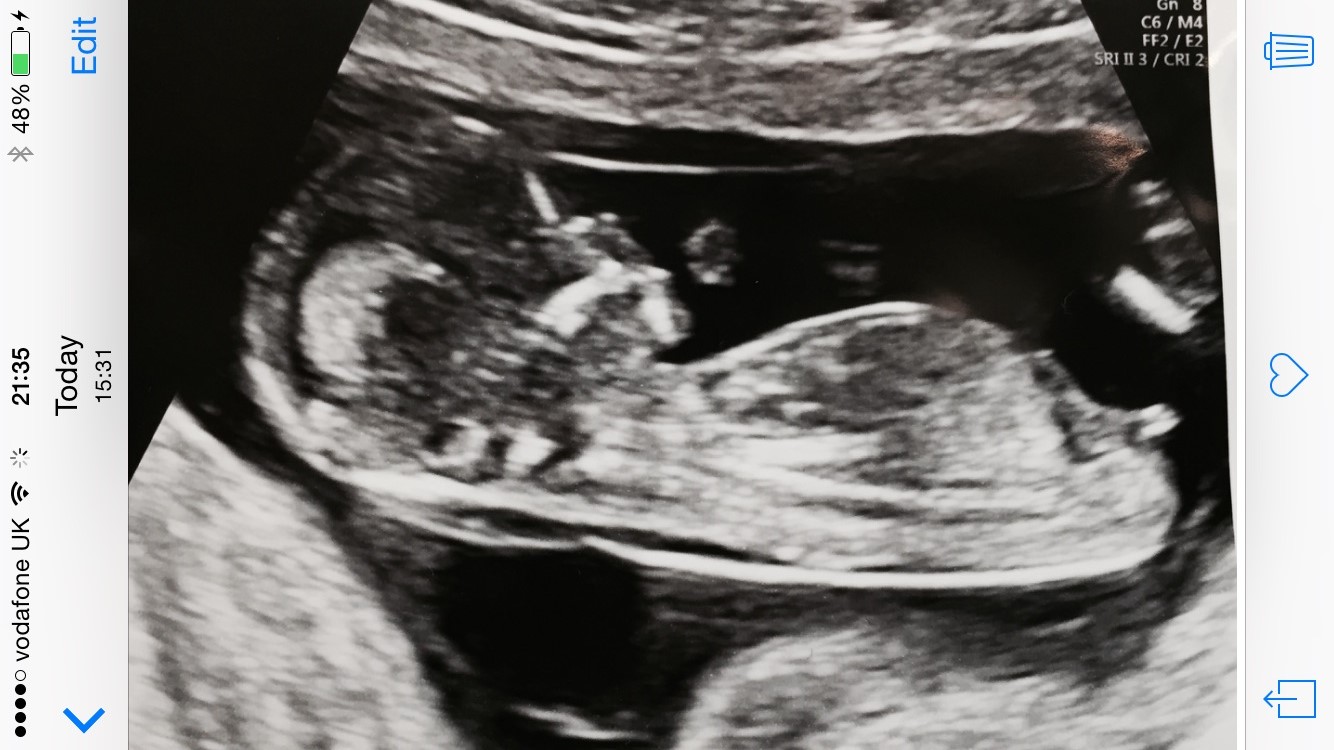

13+2

Girl!

Ooh thats a toughy I see the three line split but it also looks like its sort of angling up anyone else seeing it? Attachment 24060

Yeah I was torn too. It is angling up but not as much as I'd expect at 13 plus from a boy. I don't know either lol. Maybe boy lean.

I think boy, there's a bit of an angle